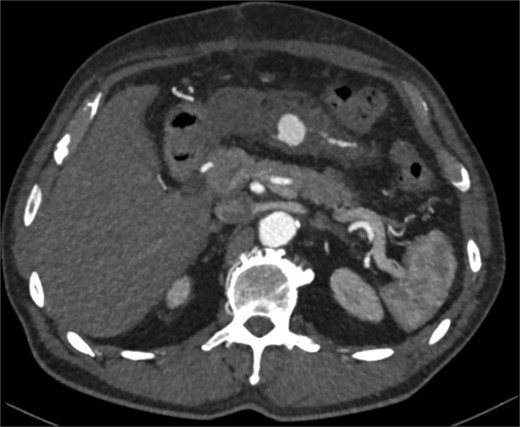

On day five post-operatively, the patient deteriorated, developing hypotension, diaphoresis, a new oxygen requirement, and complaining of new onset back pain. This is in conjunction with a drop in haemoglobin (Hb) from 129 g/L (day one post-operatively) to 89 g/L on Day 5. An abdominal CT Angiogram was performed, showing a pseudoaneurysm of the Marginal artery of Drummond measuring 1.2 × 1 × 1 cm (AP × TR × CC) with some surrounding haematoma in the small bowel mesentery (see Fig. 1). Following multi-disciplinary team (MDT) discussion, three possible management options arose: observe and re-scan the following day and optimize Hb, embolize the artery (although this has a risk of bowel infarction) or to resect the bowel. We decided to adopt a watch-and-wait approach and repeat the CTA the following day, which showed no significant change in the pseudoaneurysm. He was discharged home on Day 6 post-operatively.

CT angiogram performed on 5th postoperative day, demonstrating a small false aneurysm (1.2 × 1 × 1 cm) arising from the marginal artery of Drummond.